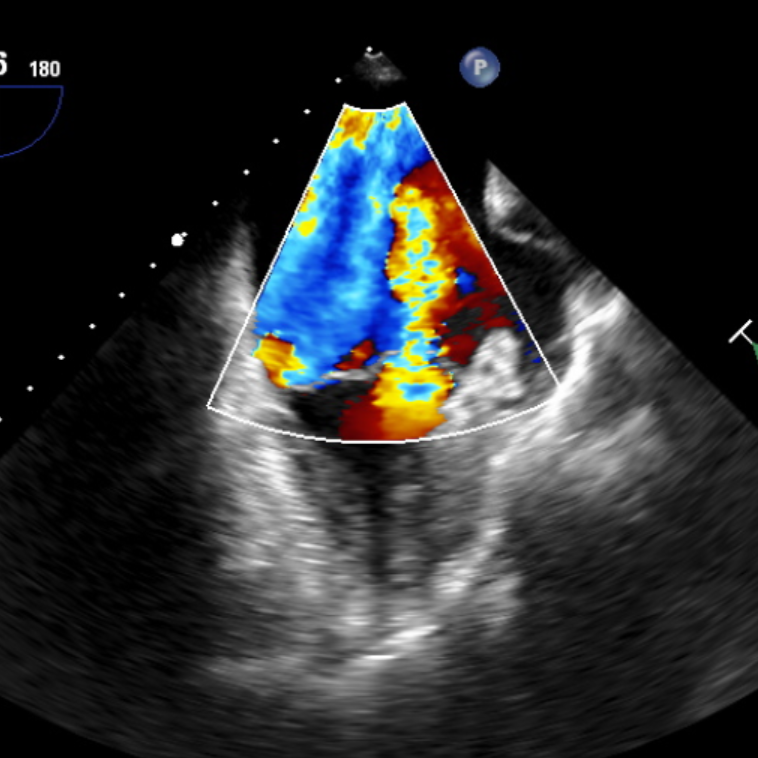

术前TEE